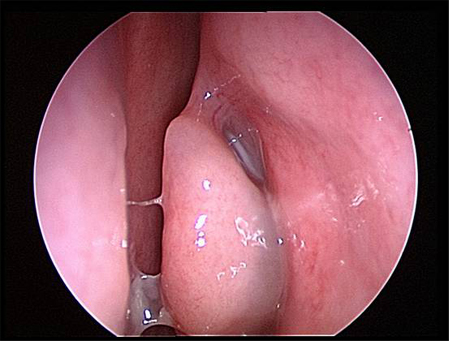

The nasal cavity should be examined for the presence of mucosal erythema or purulent discharge. Optimal exam is performed after topical decongestant spray.[18]Benninger MS, Ferguson BJ, Hadley JA, et al. Adult chronic rhinosinusitis: definitions, diagnosis, epidemiology, and pathophysiology. Otolaryngol Head Neck Surg. 2003 Sep;129(3 Suppl):S1-32. Either an otoscope or a nasal speculum and head light may be used. However, because nasal exam may be difficult or the signs nonspecific, nasal endoscopy is recommended in selected patients, including patients refractory to empiric antibiotic therapy or where there is concern for antibiotic resistance, or in immunocompromised patients.

Endoscopy can provide excellent visualization of the nasal cavity and sinus drainage paths. There are two types of endoscope: rigid and flexible. A rigid nasal endoscope has superior resolution and only requires the use of one hand. This easily allows cultures of the nasal cavity or sinus to be obtained if necessary. A flexible nasal endoscope is more comfortable for patients, but requires both hands to use. There are flexible nasal endoscopes that have a channel for collecting cultures, but these tend to be larger and more uncomfortable and they are also more difficult to reprocess. Generally, the flexible nasal endoscope is preferred in children as it is better tolerated; however, either type may be used in adults and children. Choice will depend on the practitioner's familiarity with the procedure, and most will be performed by an ear, nose, and throat specialist.

Periorbital or malar edema, orbital proptosis, visual disturbances, abnormal extraocular movements, or abnormal neurologic signs may indicate the presence of complications, and urgent otolaryngology consultation is required.[Figure caption and citation for the preceding image starts]: Right inferior turbinate and septum are visible prior to decongestant sprayFrom the collection of Melissa Pynnonen, MD [Citation ends].

[Figure caption and citation for the preceding image starts]: Right middle turbinate and middle meatus are visible after decongestant sprayFrom the collection of Melissa Pynnonen, MD [Citation ends].